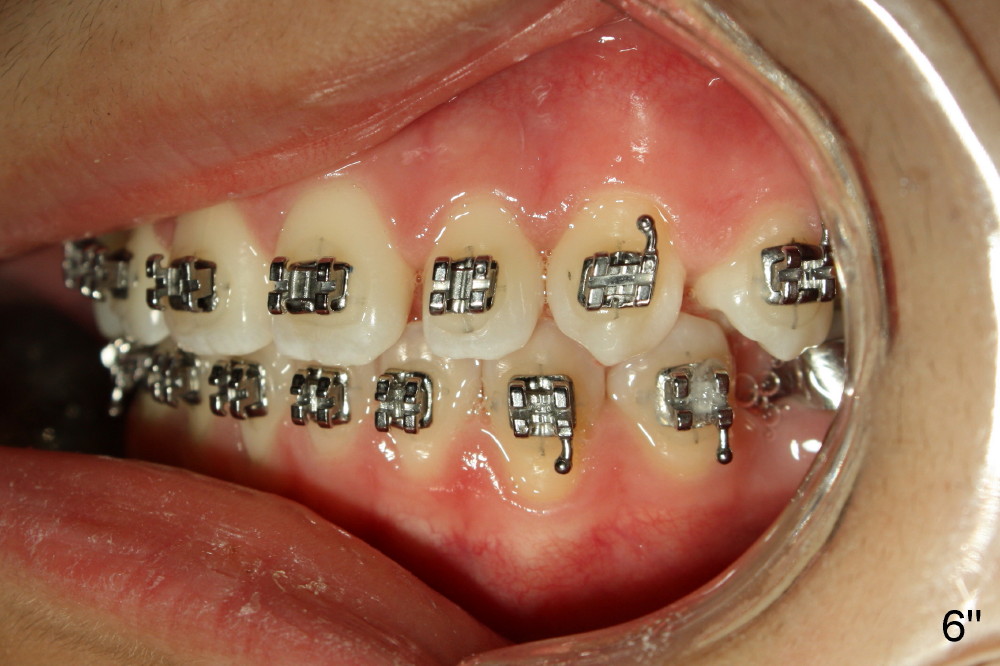

A 13-year-old Asian girl seeks orthodontic treatment for crowding. The lower 2nd bicuspids are congenitally missing (Fig.1,8), whereas the upper right one rotates 180° and the upper left is partially impacted (Fig. 1, 7). The lip muscles strain when the lips close (Fig.3). Orthodontic treatment started with extraction of four affected teeth (#4,13, K and T) 6 months ago. .018' niti wires are being used. Dental midlines do not coincide preop and intraop (Fig.4,4'). Pre-op front view shows that the upper dental midline coincides with the facial one (Fig.1'). There is Class I canine and molar relationship on the right (Fig.5,5',9,9'); open bite on the left (Fig.6,6',10,10').

Update: The left open bite was closed less than one month by wearing elastics between upper and lower teeth (Fig. 6'''). The occlusal plane and midline improve (Fig.4''). Wires have gradually changed to .016x.016, .016x.022 and now .018x.025 with power chains. All the spaces are closed except the one in LR (Fig.7''-10''). What I cannot accomplish is to fix meisal (Fig.5'' (white line), 9'') and lingual (Fig.8'' arrows) inclination of LR molars, although elastic is instructed to be placed between UR7 buccal and LR7 lingual. The rectangular wires could be twisted to fix lingual inclination. Which should be done first: LR space or LR molar inclination? Click each figure for magnification.